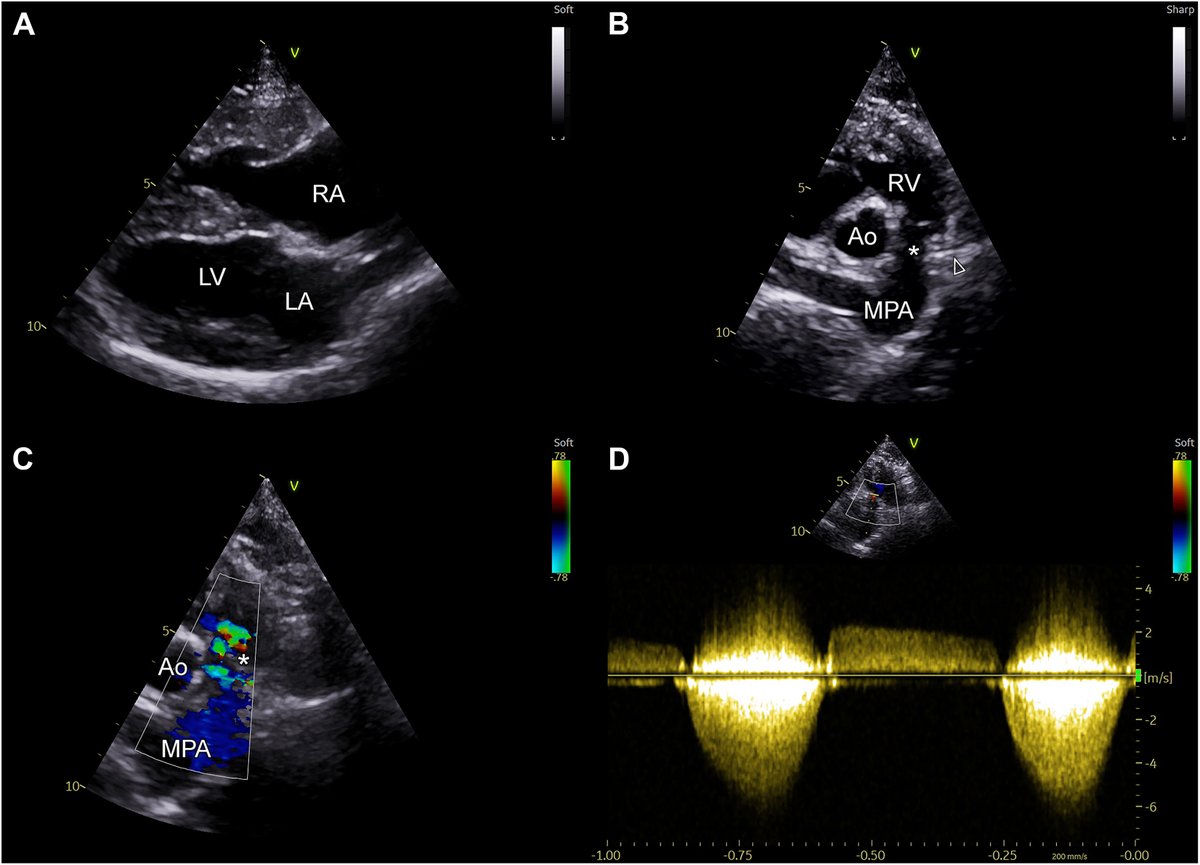

CV Case Journal retweetledi